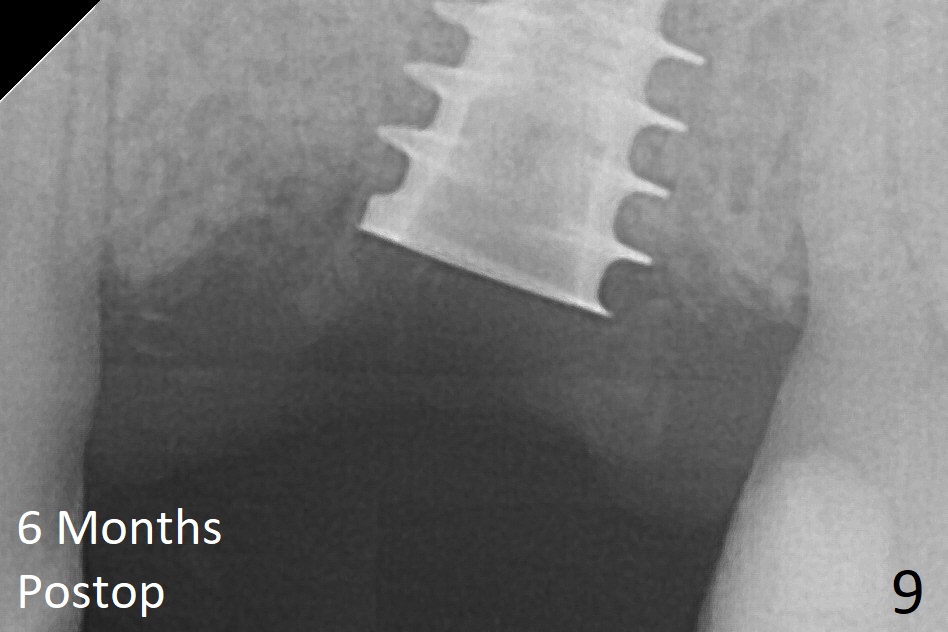

The implant is mobile 4 months postop (Fig.6). A 6x2 mm healing abutment is placed next. Although the implant remains mobile 6 months postop, the bone seems to have become denser around the implant (Fig.7-9). A healing screw is placed. When the bone height is limited (<7 mm), place a larger implant (>5.5 mm). The implant seems to have osteointegrated 8 months postop (Fig.10). Impression is taken following placing a 6.5x4(3) mm abutment. The patient reports pain after cementation, which is less when the abutment screw is loose (9.5 months postop, 2 weeks post cementation). CBCT taken after placement of a healing screw apparently shows loose bone mesial and distal to the implant (Fig.11 *). The implant trajectory is less favorable. It seems necessary to change to a large implant with more sold threads (Fig.12).